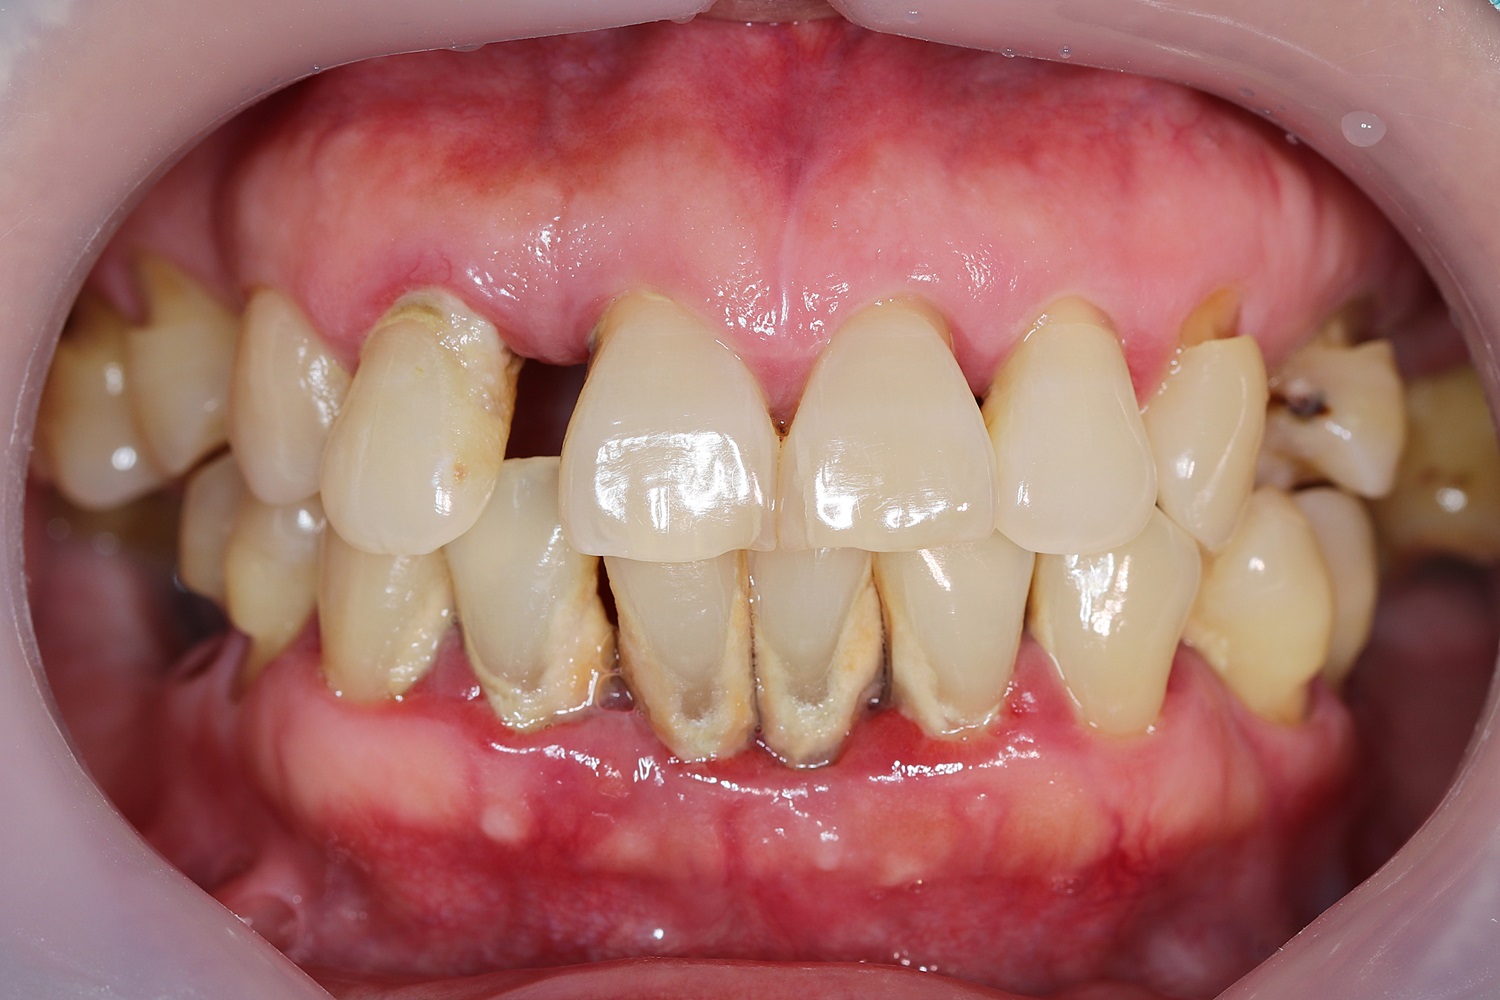

Surgical periodontal therapy is often necessary when advanced gum disease, or periodontitis, cannot be effectively managed through non-surgical treatments like scaling and root planing. Here at Prime Periodontics and Implants in McKinney, we use a variety of surgical periodontal techniques to address gum disease, repair damaged tissues, and create a healthier, more stable oral environment. These procedures aim to reduce gum pockets, eliminate bacteria, and restore both the function and aesthetics of your smile.

Reshaping the Bone to Reduce Gum Pockets: In cases where gum disease has caused the underlying bone to become uneven, osseous resective surgery may be required. This procedure involves reshaping the bone to eliminate the deep pockets that can harbor bacteria and make it difficult to keep your teeth clean. Our specialists carefully smooth and contour the bone, which allows the gums to reattach more easily and reduces the depth of the pockets. This approach not only helps control the progression of gum disease but also improves the overall structure and stability of your teeth.